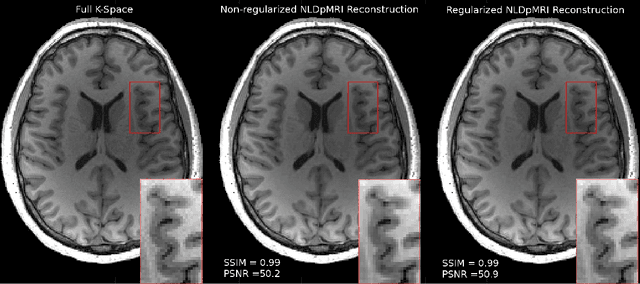

Fast data acquisition in Magnetic Resonance Imaging (MRI) is vastly in demand and scan time directly depends on the number of acquired k-space samples. The most common issues in any deep learning-based MRI reconstruction approaches are generalizability and transferability. For different MRI scanner configurations using these approaches, the network must be trained from scratch every time with new training dataset, acquired under new configurations, to be able to provide good reconstruction performance. Here, we propose a new parallel imaging method based on deep neural networks called NLDpMRI to reduce any structured aliasing ambiguities related to the different k-space undersampling patterns for accelerated data acquisition. Two loss functions including non-regularized and regularized are proposed for parallel MRI reconstruction using deep network optimization and we reconstruct MR images by optimizing the proposed loss functions over the network parameters. Unlike any deep learning-based MRI reconstruction approaches, our method doesn't include any training step that the network learns from a large number of training samples and it only needs the single undersampled multi-coil k-space data for reconstruction. Also, the proposed method can handle k-space data with different undersampling patterns, and different number of coils. Unlike most deep learning-based MRI reconstruction methods, our method operates on real-world acquisitions with the complex data format, not on simulated data, real-valued data, or data with added simulated-phase. Experimental results show that the proposed method outperforms the current state-of-the-art GRAPPA reconstruction method.